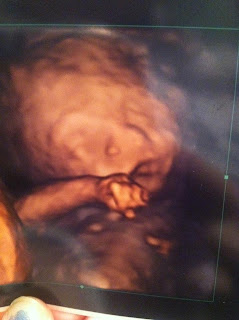

and here are our last pictures from last appointment 25 weeks 5 days he looks just like his daddy already !!

2 days later after i seen Dr Ortiz i got scheduled to see the fetal specalist (october 10,2011) Dr. Barsoom. Chris had taken the day off for us to go down to the doctor and find out what was going on just having hope that we would get news his legs could be fixed after he was born. We got to the office, got registered and sat there and waited to get called back filled with so many different emotions.. sad,lost,stressed,worried, and hopeful. Finally we got called in and the nurse did a full ultrasound and we got to see our baby on a 52 inch screen tv. She measured out ALL of the baby's bones and than we got to see a 3d picture of our baby. We liked that we were getting to see her/his beautiful face on the big screen but we will still worried/scared to hear what doc was going to give for us for information on his legs. After she had gotten done with measuring the baby she told us it would be just a few minutes for the doctor to come in. When he came in he started to tell us news that was SO unexpected.. that his leg bones were not only bent but his arms and legs were excessively short and that in a case like this he thinks that our baby has campomelic dysplasia which is a form of skeletal dysplasia. Chris and I just sat there at loss of words sad and heartbroken. As we sat there and listened the doctor told us that he was going to do an ambio santicas on me so that we could get exact results of what was wrong with our baby as to if it was a chromosonal deal and if it was skeletal dysplasia. He told us we could terminate the pregnancy or carry it to term and asked if we had any questions. Chris and I were still at loss of words and i was to sad to even talk and had been bawling for a while now but chris's mom started asking questions "well what are the chances of the baby living if they do carry it to full term?" "what is the quality of the childs life going to be" ect. and dr barsoom began answering telling us that if the baby lives outside of the womb and has Campomelic Dysplasia they only have a 5 percent chance of living and if the child does survive will have breathing trouble the rest of his/her life. I told him that we just needed to go home and would have answers for him after we had gotten the amnio results back. He had began doing the amnio to get a more exact diagnosis of what was going on with our child. I began wondering IF our baby was going to have physicical disabilities and if it was even right to bring he/she into this harsh world if he/she was going to have so many problems. After we were done with the amnio the doctor told us that he would give us a call in a few weeks with our results of the diagnosis and we could make our decisions. Chris and I than left the hospital and came home. I was clearly a mess by this time bawling my eyes out. We talked about it on the way home as to our decision but we just didnt have an answer to what we were going to do .. at first we thought about terminating the pregnancy before the 24 weeks IF we did get results that he had campomelic dysplasia because we didnt want our child suffering in this harsh world if he didnt get to have a good quality of life. I had so many mixed emotions at the time.. Felt guilty as to terminating the pregnancy and wondering if it wasnt right ect. We talked about how would we ever be able to raise a disabled child when we dont have the income for it ?? all kinds of different things but we just had to try not to stress and hope for the best while waiting for the results.